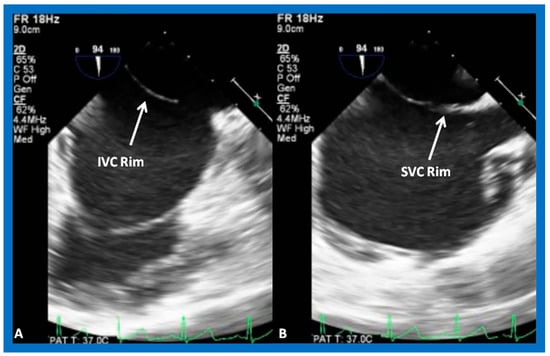

8.5. Septal Rims